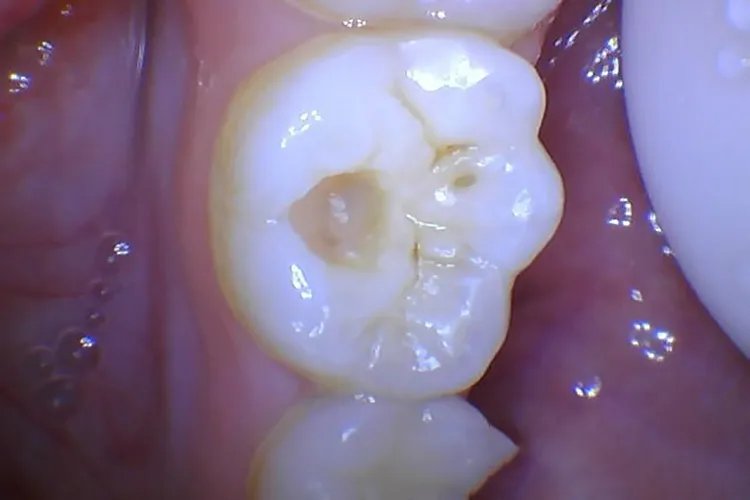

中龋病变已到达牙本质浅层,龋损部位牙本质呈黄褐或深褐色,龋洞形成,牙体缺损明显,病变牙本质质地较软,患者对酸甜刺激敏感,过冷过热饮食也能产生酸痛感觉,冷刺激尤为显著,但刺激去除后症状立即消失。

深龋龋洞深大,达牙本质深层,龋损部位牙本质呈黄褐或深褐色,牙体缺损明显,病变牙本质质地较软,当食物嵌塞入龋洞中或患牙遇冷、热、酸、甜、化学刺激时可出现疼痛,去除刺激后症状立即消失。